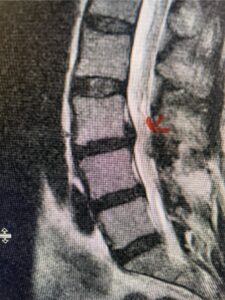

Fig 4: Sagittal T2-weighted lumbar MRI demonstrating an L4-5 grade 1 spondylolisthesis with obvious emanation of the disc herniation from the L4-5 level (red arrow)